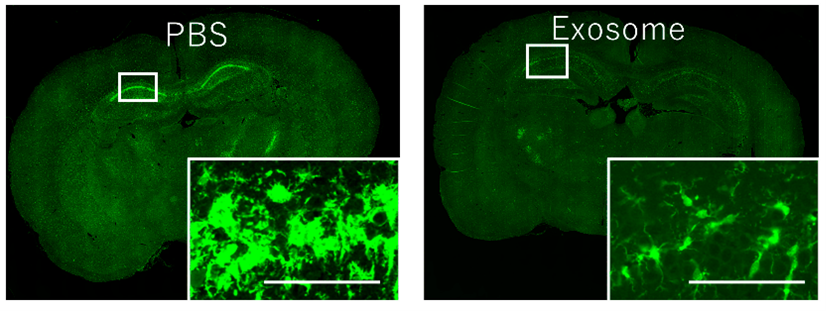

使用Anti Iba1, Rabbit抗体对iba1进行染色,评估海马体中的小胶质细胞活化情况。

海马体中的小胶质细胞激活。在PBS处理组中可明显观察到活化的小胶质细胞(增殖与形态转变),而外泌体处理组则有效抑制了这种激活。